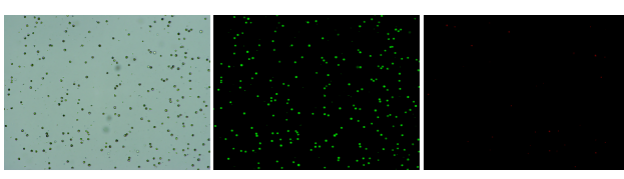

人肝癌樣本,懸液背景干凈,活性91.69%,結(jié)團率6%